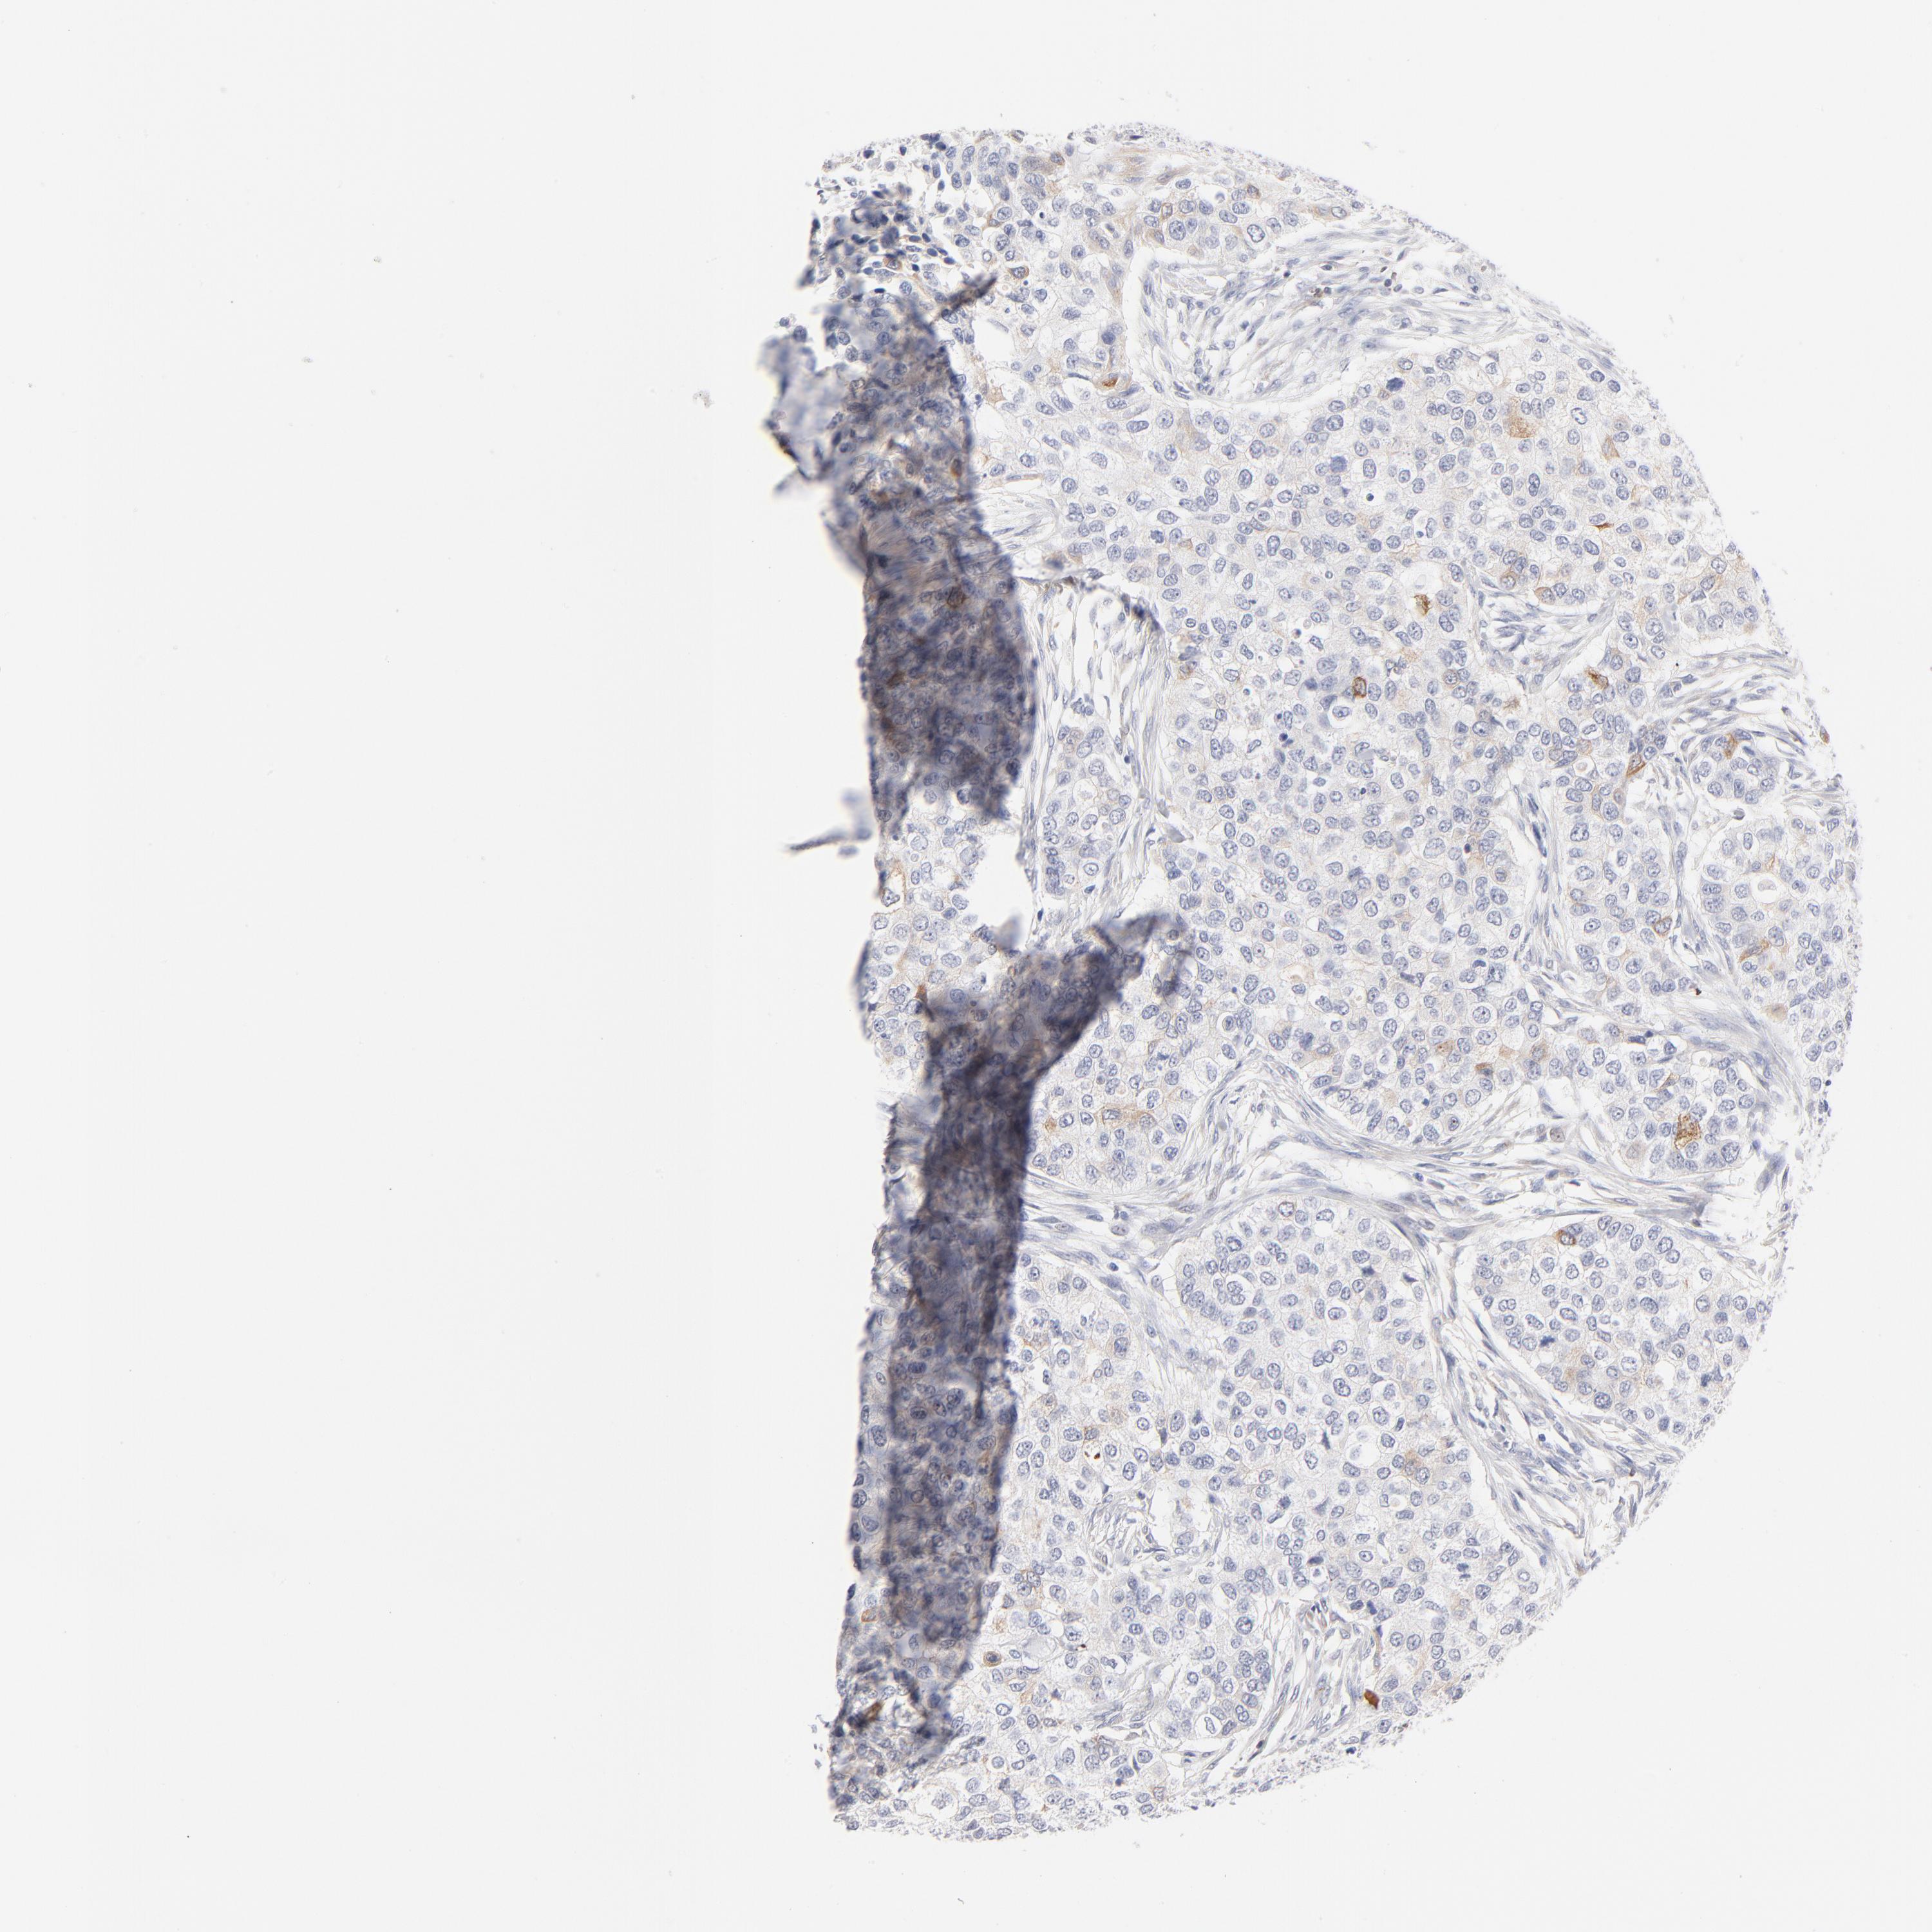

CANCER BREAST CANCER Show tissue menu

BRCA TCGA BRCA VALIDATION PROTEIN EXPRESSION

ANTIBODIES

AND

VALIDATION